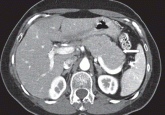

ArticleAutoimmune pancreatitis: A mimic of pancreatic cancerAuthor:David Vogt, MDPublish date: October 1, 2009The accurate and timely diagnosis of this benign disease may preempt the misdiagnosis of cancer and decrease the number of unnecessary pancreatic r...Read More